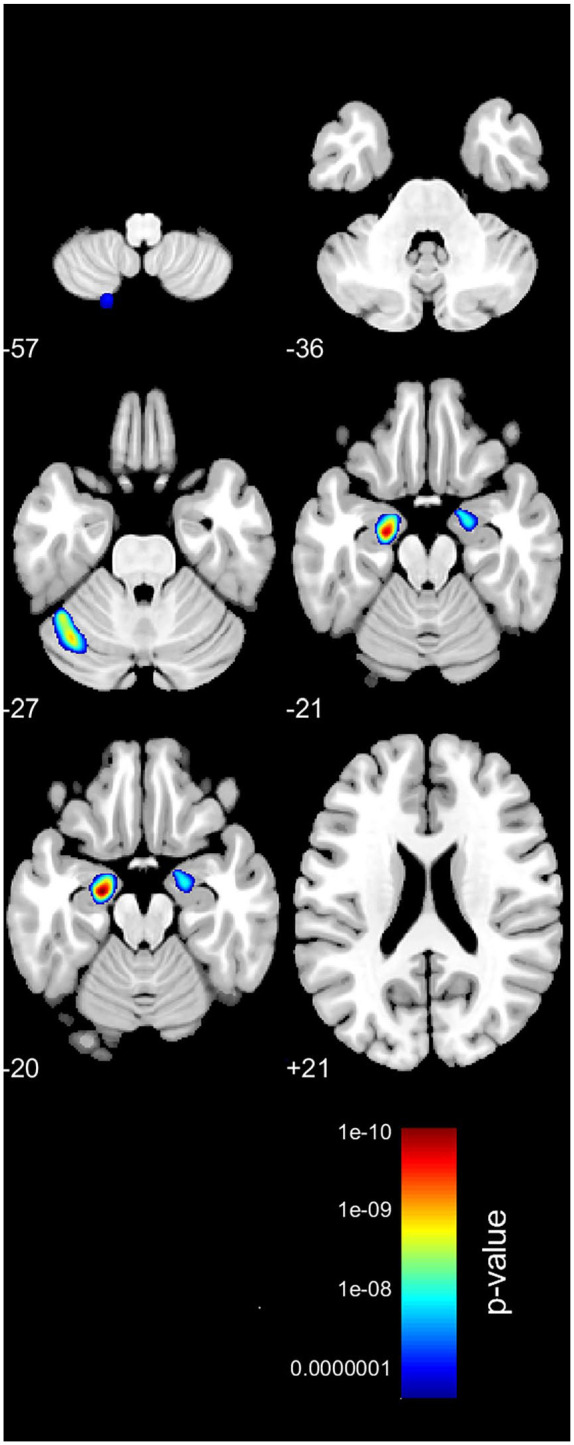

Results: We have found differences in grey matter volumes in the bilateral anterior hippocampus (left P < .001 and right P = .01) and left cerebellum exterior (Crus I) (P < .001). We have also found differences in cortical thickness in the bilateral parahippocampal gyri (left P = .001 and right P = .005) and right orbitofrontal cortex (OFC) (P < .001).